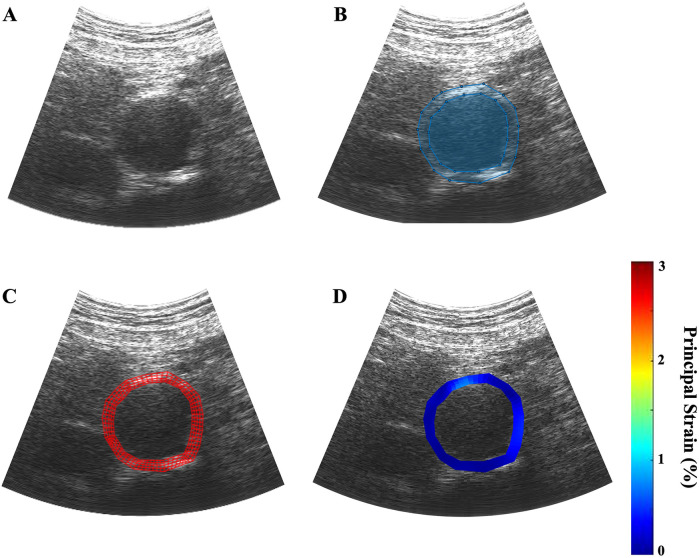

Introduction: Aortic principal wall strain is a biomechanical parameter correlated with aneurysm growth rate that affects abdominal aortic aneurysm (AAA) stability. Characterize changes in pressure-normalized maximum mean aortic principal wall strain ( ε ρ + ¯ / PP ) using ultrasound elastography (USE).

Methods: Axial ultrasound images of patient AAAs were collected at two consecutive clinic visits. The ε ρ + ¯ / PP for each image was calculated using a novel finite element mesh technique. The cohort was separated by index ε ρ + ¯ / PP terciles, and the rate of strain change, growth, intervention, and rupture were compared.